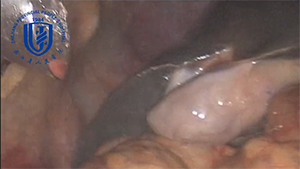

困难腹腔镜胰十二指肠切除术

作者:李国林 | 作者单位:中山大学孙逸仙纪念医院